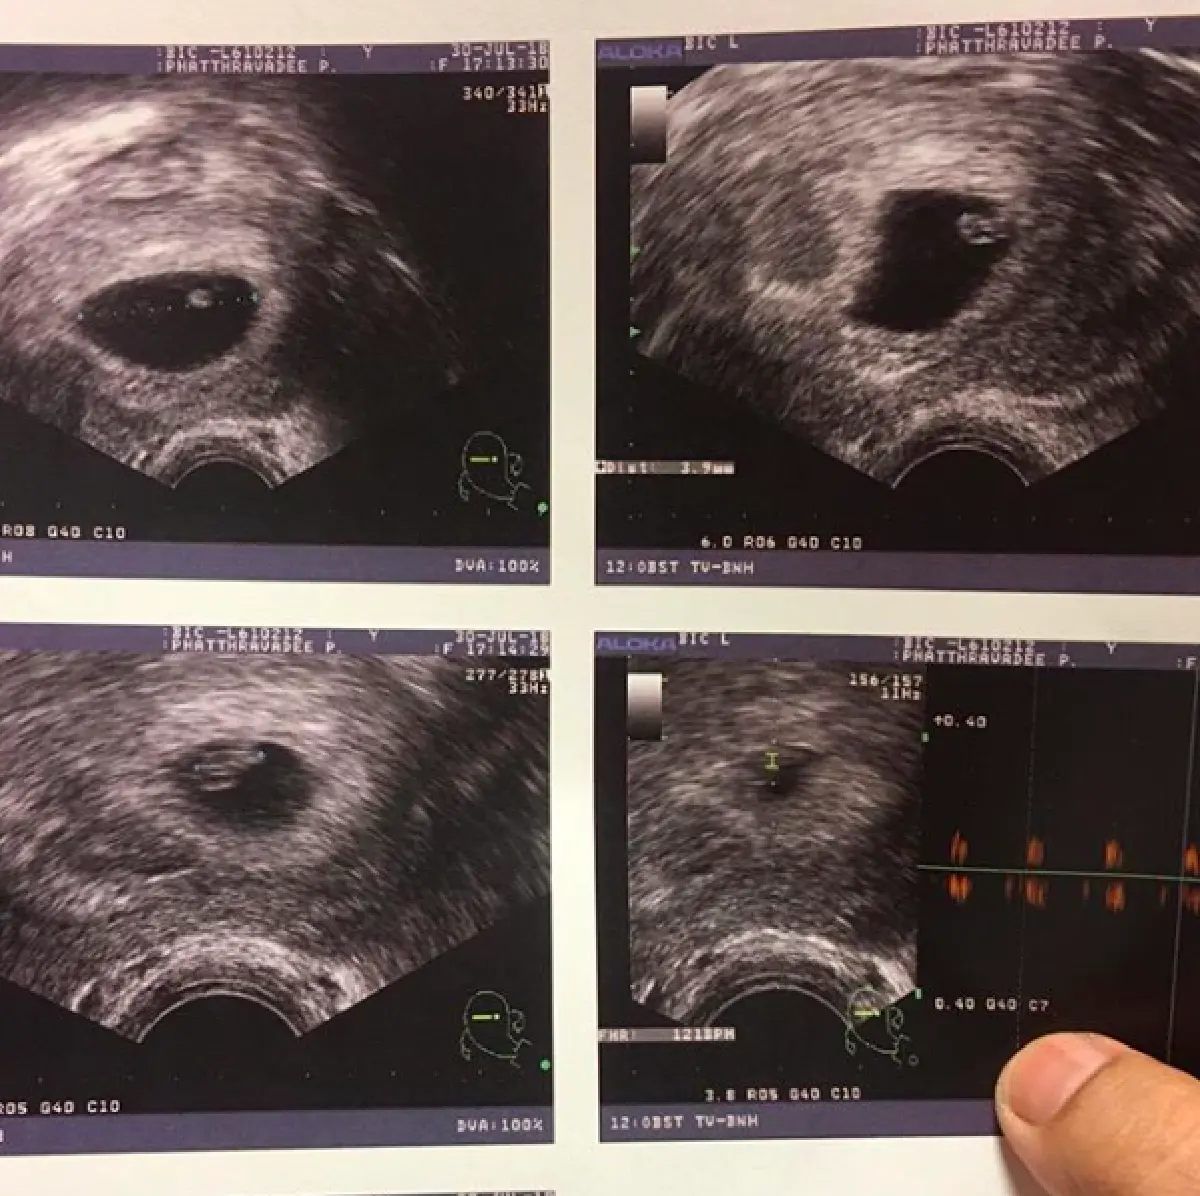

ซึ่งถ้าย้อนกลับไปเมื่อเดือนที่ผ่านมา “หนูเล็ก” นั้นได้มาเล่าความฝันให้ผู้ที่ติดตามทางอินสตาแกรมช่วยตีเลขเด็ด แต่หลายๆ คน ต่างบอกว่าความฝันของเธอเหมือนคนกำลังจะมีโชค หรือตั้งท้อง จนถึงขั้นอาจจะได้ลูกแฝดเลยทีเดียว มาวันนี้ทางฝ่ายสามี “เอก" ได้ออกมาประกาศข่าวดี ด้วยการโพสต์ภาพอัลตร้าซาวด์ พร้อมข้อความว่า "ไอ้แสบของพ่อมาแล้วครับผมมมม ตัวเล็กนิดเดียวแต่แสบเหลือเกิน ทำแม่กินไม่ได้นอนไม่หลับอ้วกตลอดเวลา เบาๆ หน่อยสงสารแม่นะครับแสบ ดีใจจังคริคริ 6 weeks ครับ"

ซึ่งทาง “หนูเล็ก” เอง ก็ได้ออกมาโพสต์เหมือนกันว่า "ตัวเล็กมาเป็นของขวัญวันเกิดพอดีคะ มาปุ๊บก็แพ้หนักมาก อ้วกทั้งวัน เวียนหัว24 ชม. นอนเวียนหัว ลุกขึ้นก็อ้วก ตอนนี้ไม่กล้ามองกระจกแล้ว ช่วงนี้คงห่างหายจากหน้าจอ เพราะทำอะไรไม่ได้เลยคะ ได้ยินเสียงหัวใจเค้า เราก็จะต้องอดทนถึงแม้จะทรมานเหลือเกิน”